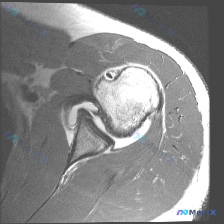

整理了一份肩部MRI病例讨论材料,医生的核心问题是排查盂唇病变,但看影像发现了一些矛盾点。先放MRI T2序列冠状位的分析: 1. 骨性结构:肱骨头、肩峰及锁骨远端轮廓尚可,未见骨折线或骨髓水肿 2. 肌腱与肩袖:冈上肌腱在肱骨大结节止点处形态异常,连续性中断,T2高信号 3. 关节与滑囊:肩峰下-...

最近整理了一份肩部MRI的病例讨论材料,患者主要问题是肩部疼痛,但问题明确指向"盂唇病变"范畴。先看T2冠状位图像的关键发现: 1. 冈上肌腱在肱骨大结节止点处有显著高信号,连续性可能中断 2. 肩峰下-三角肌下滑囊有明显的高信号积液 3. 关节盂唇区域信号存在改变 大家觉得这个病例更符合哪种诊断?...

看到一个肩部MRI(冠状位)的病例资料,用户最初的问题是关于「盂唇病理」,但整理的分析报告里有几个点挺值得讨论的: 先放影像的关键发现: - 冈上肌腱连续性中断,断端回缩,伴冈上肌肌腹萎缩、脂肪浸润 - 肩峰下-三角肌下滑囊积液,肩峰下间隙变窄,肱骨头上移 - 肱骨头大结节下方骨髓水肿 - 盂唇形态...

看到一个肩关节MRI病例资料,有个比较有意思的点:用户的问题是「What is the noticeable abnormality in this image?Labral pathology」(图像中明显的异常是什么?盂唇病变),但整理的影像分析报告核心发现是冈上肌腱全层撕裂。 先把报告里的关键...

看到一个肩关节MRI影像分析的病例材料,影像为冠状位T2加权图像,主要发现如下: 1. 冈上肌腱远端附着处全层撕裂,T2序列显示高信号液体填充 2. 肩峰下-三角肌下滑囊内有明显积液 3. 盂肱关节腔内有显著液体潴留 用户的核心问题是关于「盂唇病变」的可能性。这个病例有几个点值得讨论: - 冈上肌腱...